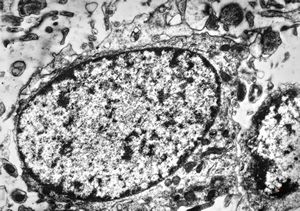

F,3y. | toxoplasmosis